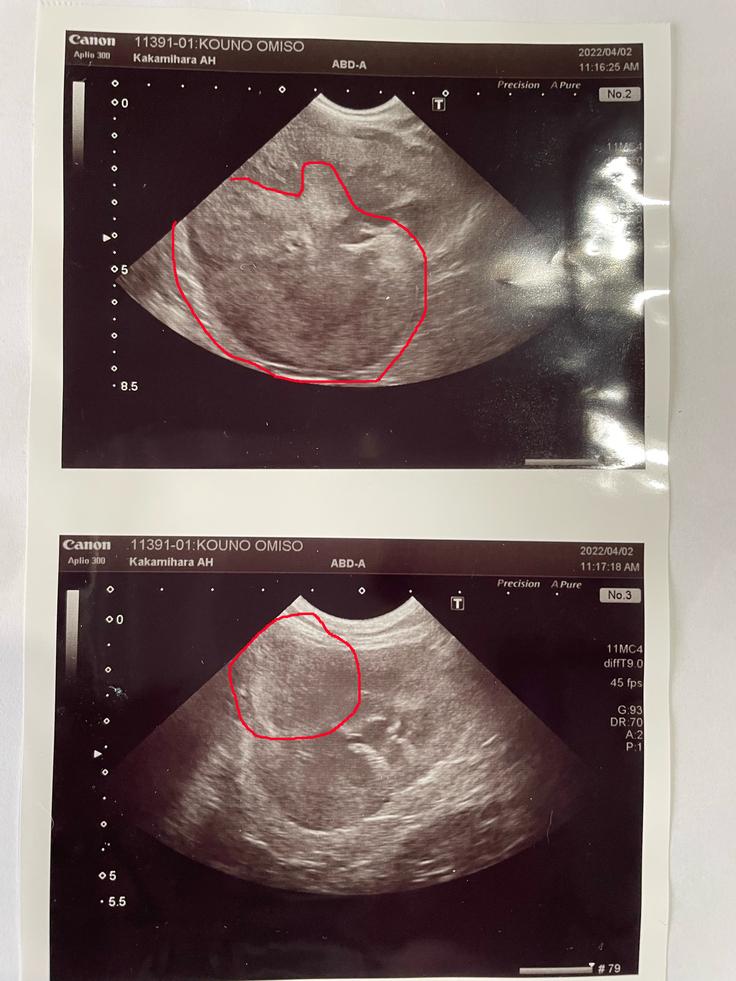

上の写真が右の腎臓

腫瘍の大きさが8センチもあるそうです。

下の写真が左の腎臓

こちらは、小さいですが。

初めはステロイド等の投薬で痛みを抑えたりできるのですが、効果は2・3ヶ月ほどのようです。腎臓のがんは、進行すれば骨髄から脳の方へ転移し、やがて目が見えなくなり、嘔吐や痙攣を引き起こすそうです。なので、抗がん剤治療は早めの処置が良いとの事。週一回の投与を最低25週、一回の投与が2万円程で25週で約50万円程かかるみたいです。